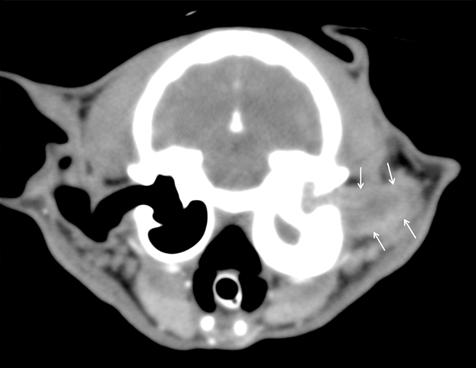

En la exploración otológica se visualizó una masa en el conducto auditivo externo izquierdo, apreciable desde la abertura del pabellón auricular. La masa era sólida, poco móvil y obstruía totalmente el canal auditivo. El resto del examen físico y pruebas de enfermedades víricas fueron normales. En el análisis sanguíneo se evidenció neutrofilia con desviación a la izquierda y trombocitosis.

1. Radiografías de la cabeza de un gato maine coon de un año de edad. (A) Proyección lateral. (B) Proyección dorsoventral. (C) Rostro 10º ventrodorsocaudal oblicua.